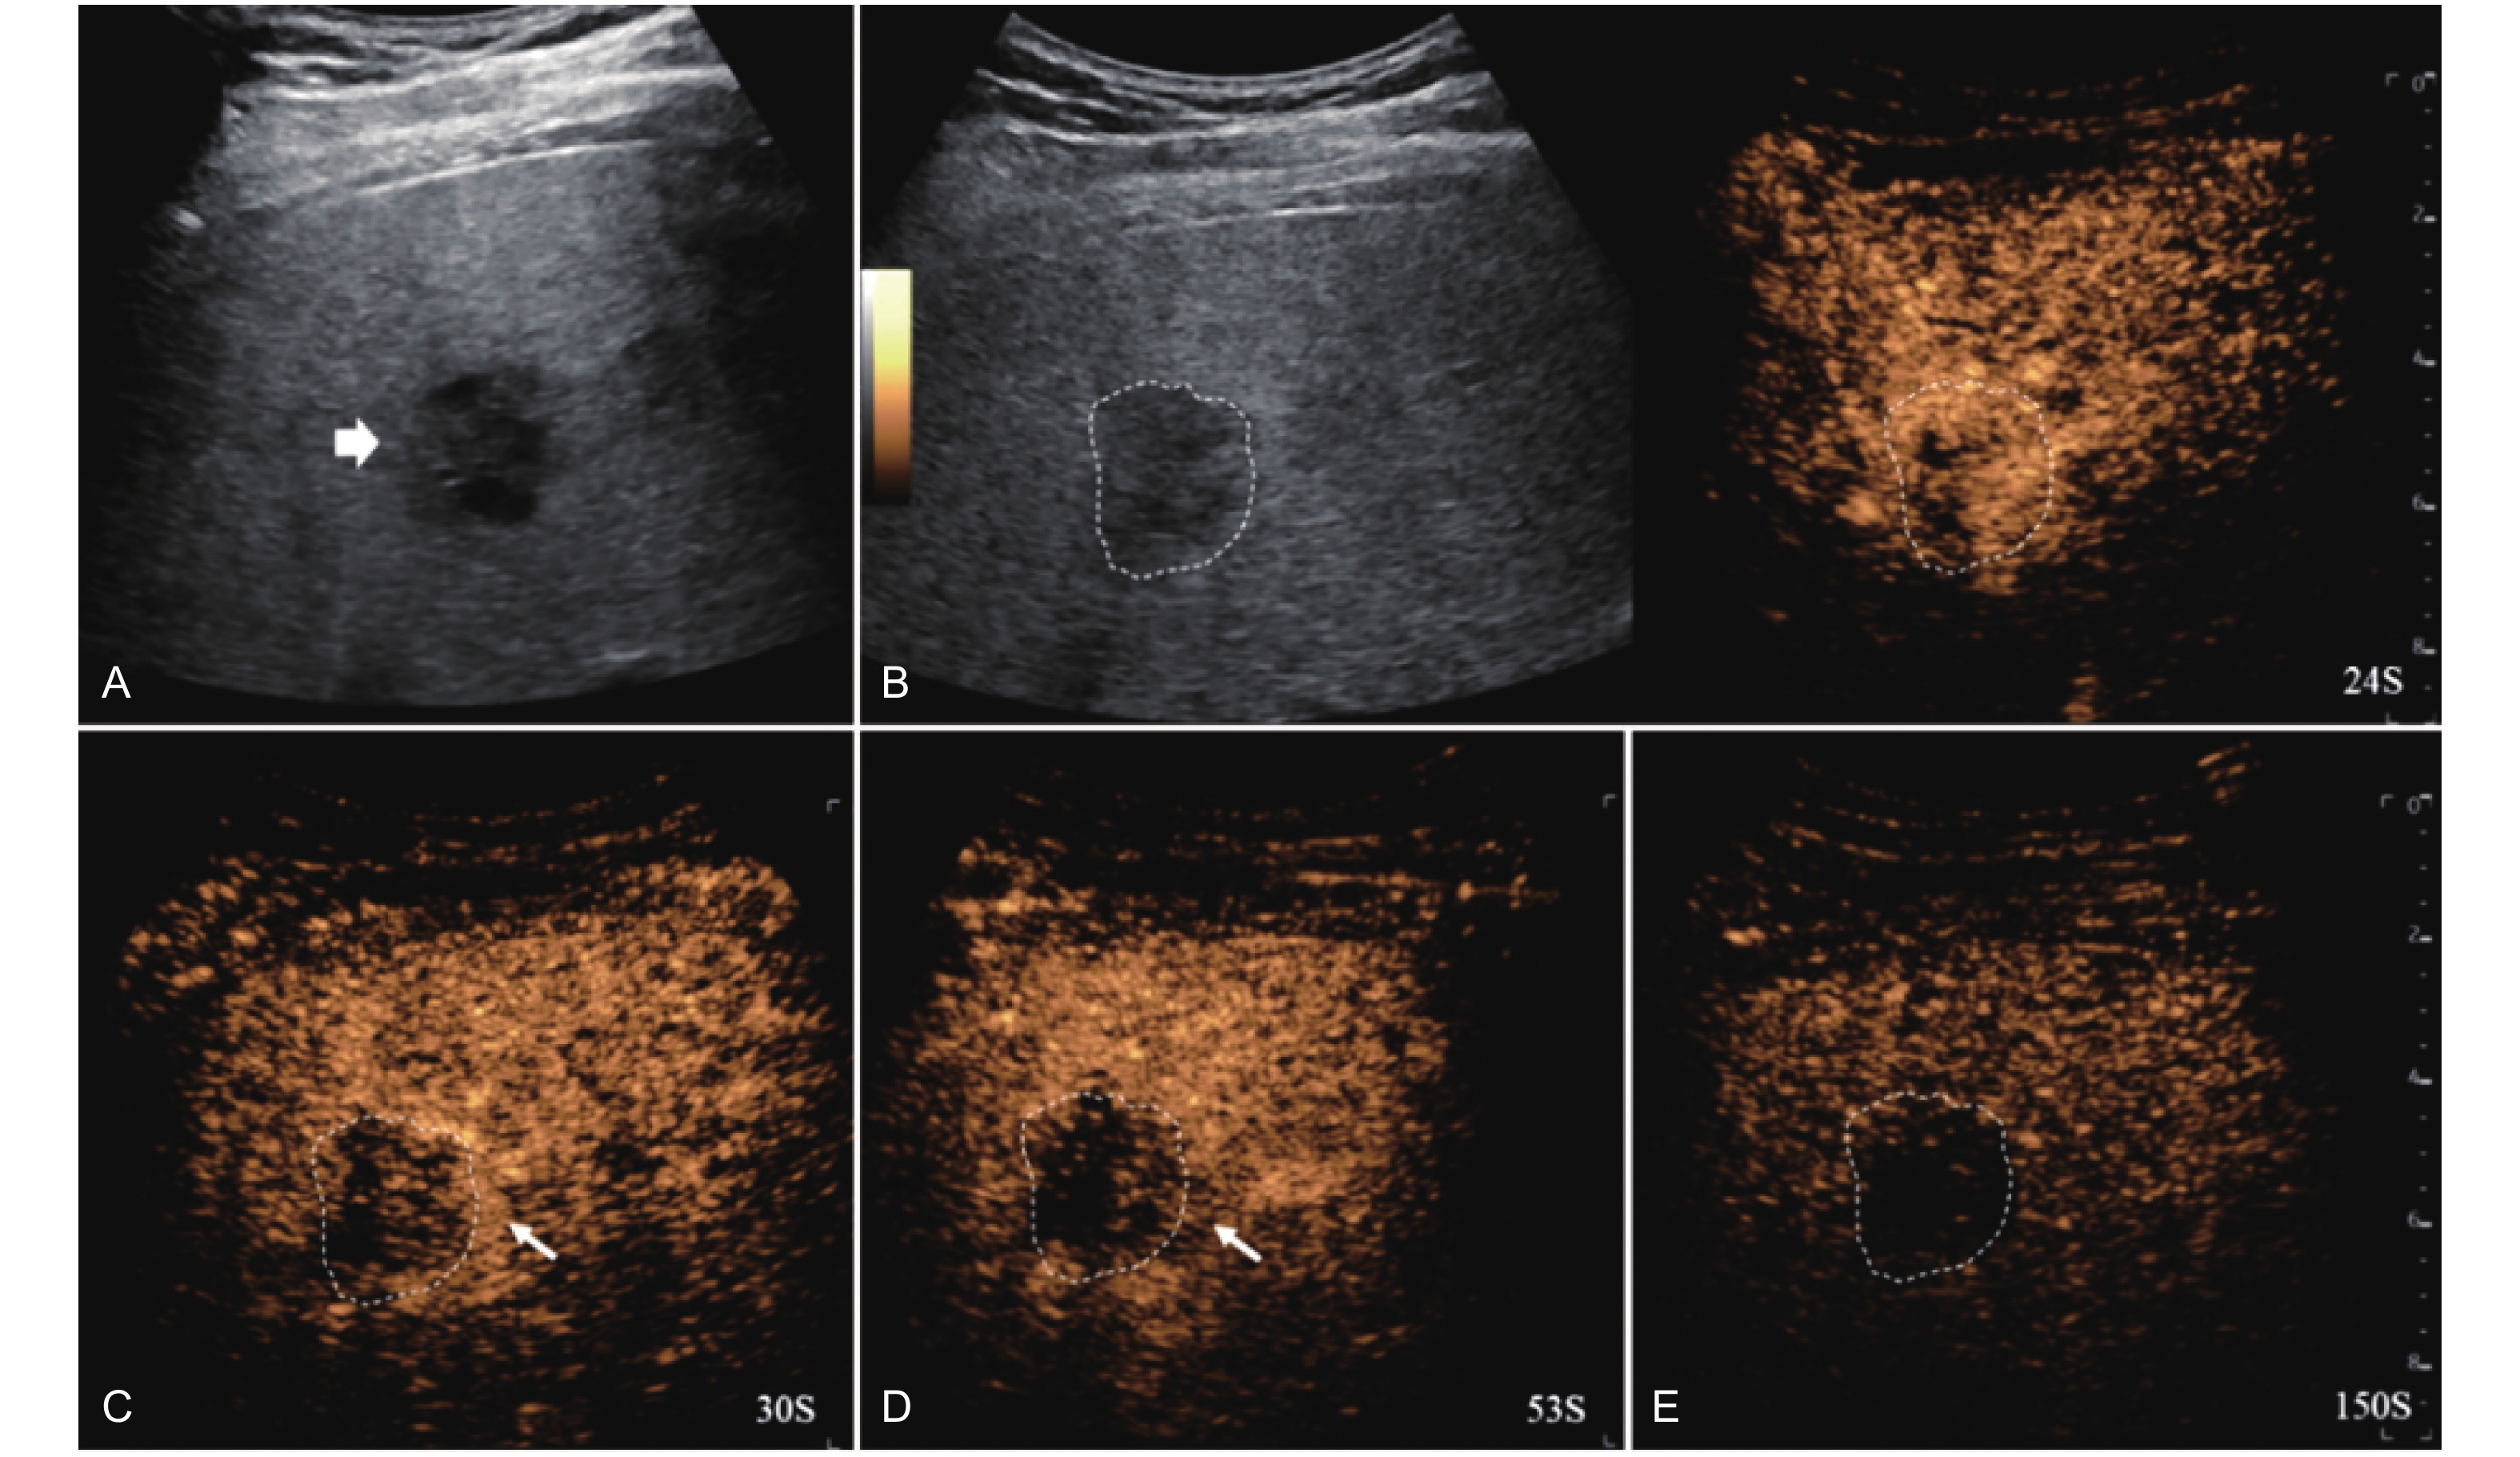

Figure 4

LR-TR Nonviable. Example of a nonviable tumor 14 days after TACE. (A) B-mode image shows two heterogeneous hyperechoic lesions (thick arrow) with irregular shape, measuring 17 mm and 18 mm in segment VI; (B-E) CEUS shows no intralesional enhancement with perilesional enhancement identical to the surrounding liver parenchyma in all phases. Findings are consistent with LR-TR Nonviable."